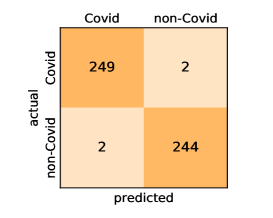

Here, we present and discuss the obtained results for detecting COVID-19 on the considered CT image datasets with different deep networks. We report the quantitative results along with the confusion matrices for every single architecture of the adopted networks.

Our models achieve fairly good performance compared with the recently published work using the exact network architectures. This can bet attributed to a better optimization of our models and the effectiveness of our fine-tuning strategy using custom-sized inputs determined specifically for each architecture. Here, we see that DenseNet201 outperforms all other architectures. The model achieves average accuracy and sensitivity scores of and , respectively. It also identifies all COVID-19 images with only four images, on the average, are falsely predicted as Non-COVID-19. DenseNet169 achieves the second best average accuracy of and a very high sensitivity identical to the best model. The DenseNet121 and Xception models have nearly identical results for all evaluation metrics. We observe that small-sized networks such as ResNet18 achieves comparable results with other deeper models. The SqueezeNet and ShuffleNet models perform at a similar level of accuracy. The variants of the ResNeXt models have comparable results and perform as good as the different ResNet variants. A detailed analysis on the class-wise results for individual models is presented in the confusion matrices in Figure 10.